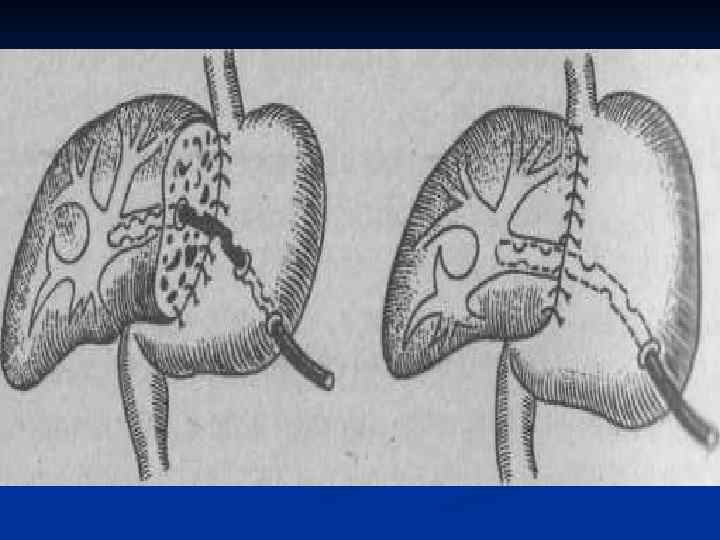

I. Восстановительные операции (восстановление проходимости протоков) 1. Эндобилиарные вмешательства под УЗИ или R – контролем (бужирование, баллонная дилатация, стентирование протоков). 2. Пластика стриктуры 3. Иссечение стриктуры с наложением анастомоза. II. Реконструктивные операции (наложение билиодигестивных анастомозов) 1. Анастомозы внепеченочных желчных протоков: а) с двенадцатиперстной кишкой (ХДА) б) с тощей кишкой (гепатико-, холедохоеюноанастомозы по Ру или по Брауну). 2. Анастомозы внутрипеченочных желчных протоков с сегментом тощей кишки, выключенной по Ру или желудком при высоких стриктурах

I. Восстановительные операции (восстановление проходимости протоков) 1. Эндобилиарные вмешательства под УЗИ или R – контролем (бужирование, баллонная дилатация, стентирование протоков). 2. Пластика стриктуры 3. Иссечение стриктуры с наложением анастомоза. II. Реконструктивные операции (наложение билиодигестивных анастомозов) 1. Анастомозы внепеченочных желчных протоков: а) с двенадцатиперстной кишкой (ХДА) б) с тощей кишкой (гепатико-, холедохоеюноанастомозы по Ру или по Брауну). 2. Анастомозы внутрипеченочных желчных протоков с сегментом тощей кишки, выключенной по Ру или желудком при высоких стриктурах